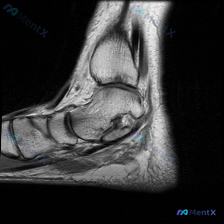

这是一张踝关节MRI T1加权序列的正中矢状位图像,图像质量清晰,结构对比度好,无明显运动伪影,可以清晰辨认胫骨远端、距骨、跟骨、舟骨等骨性结构。

- 骨信号异常:胫骨远端前部、距骨穹窿骨皮质下可见局灶性低信号异常,其余骨髓信号都是正常的脂肪高信号,骨皮质低信号边缘完整

- 关键异常区域:距骨穹窿可见明显的皮质下囊状低信号改变,累及范围清晰,周围骨性轮廓轻微不平整;对应的胫骨远端关节面也有类似的不规则低信号改变,存在软骨下骨质破坏或囊性变表现

- 软组织改变:距骨前方及关节间隙周围可见少许低信号影,考虑可能为关节腔内积液或增生滑膜,未见明显软组织肿块

- 关节对位关系正常,无明显脱位征象